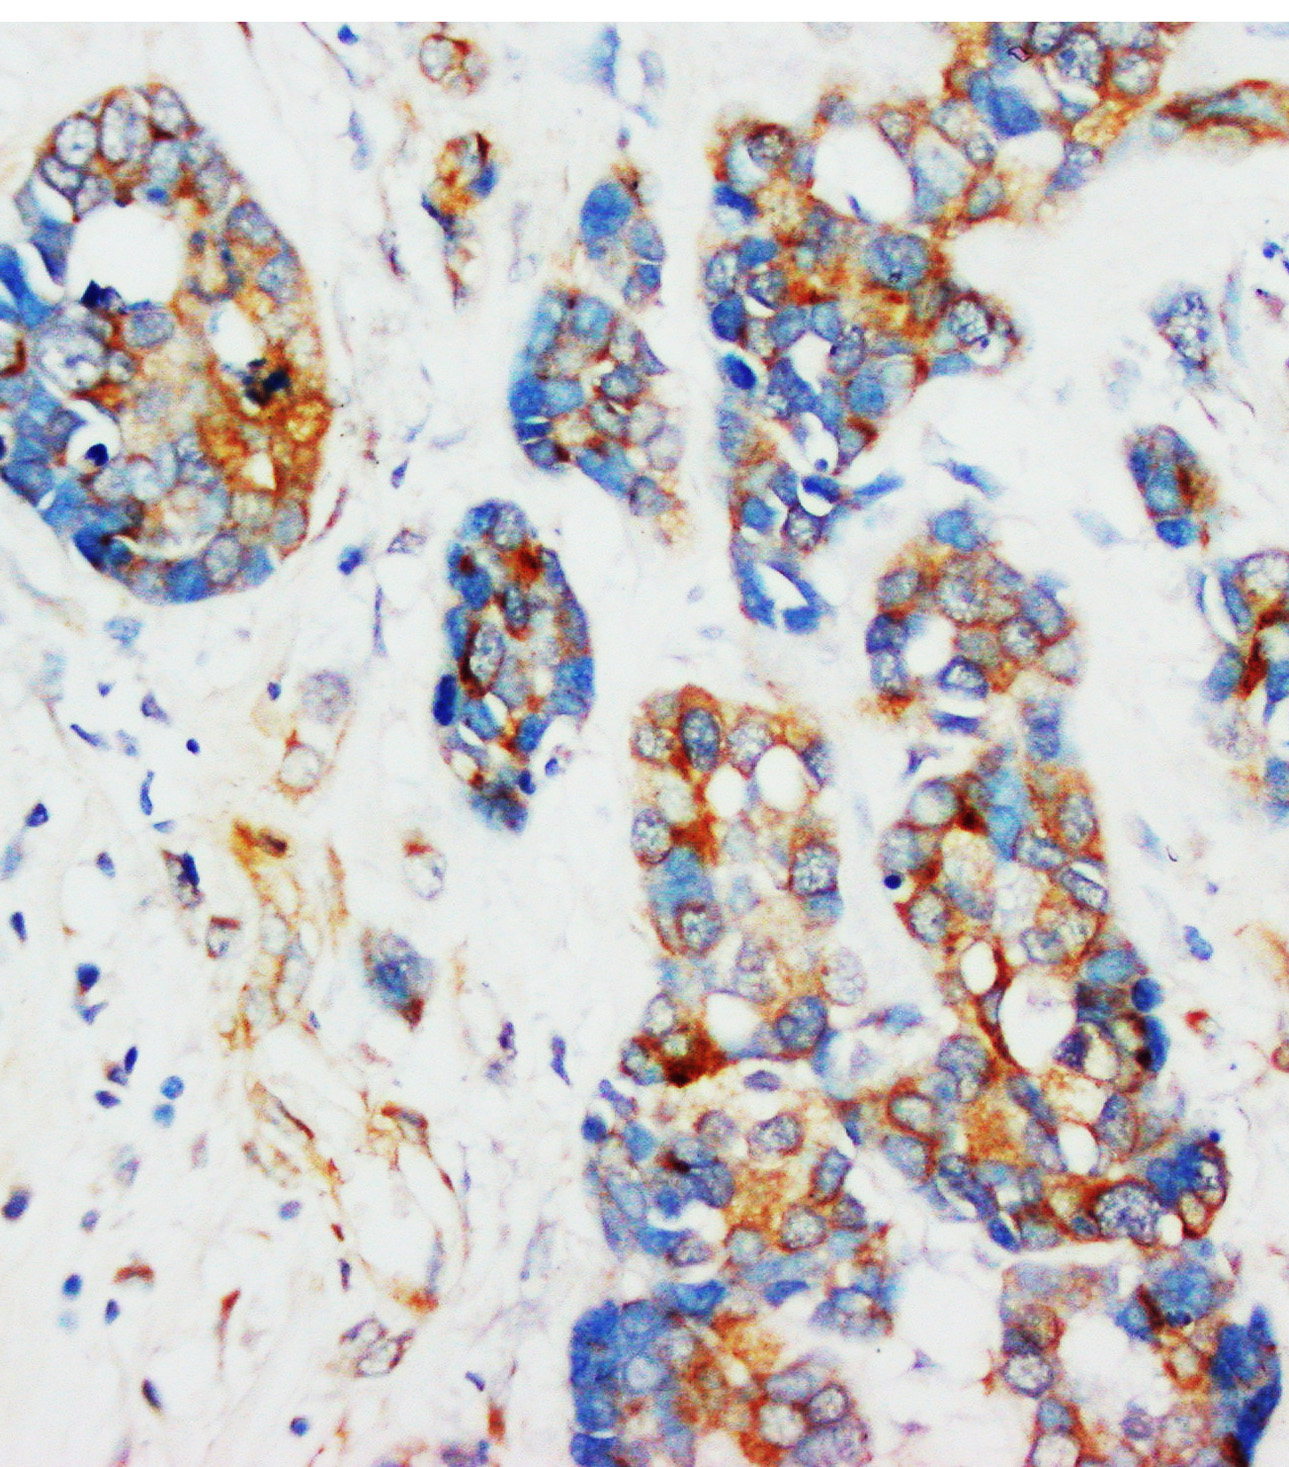

• IHC analysis using anti- β-Actin antibody (BM0627).detected in paraffin-embedded section of Human Intestinal Cancer tissue. Biotinylated goat anti-mouse IgG was used as secondary antibody. The tissue section was developed using Strepavidin-Biotin-Complex (SABC) (Catalog # SA1021) with DAB as the chromogen.